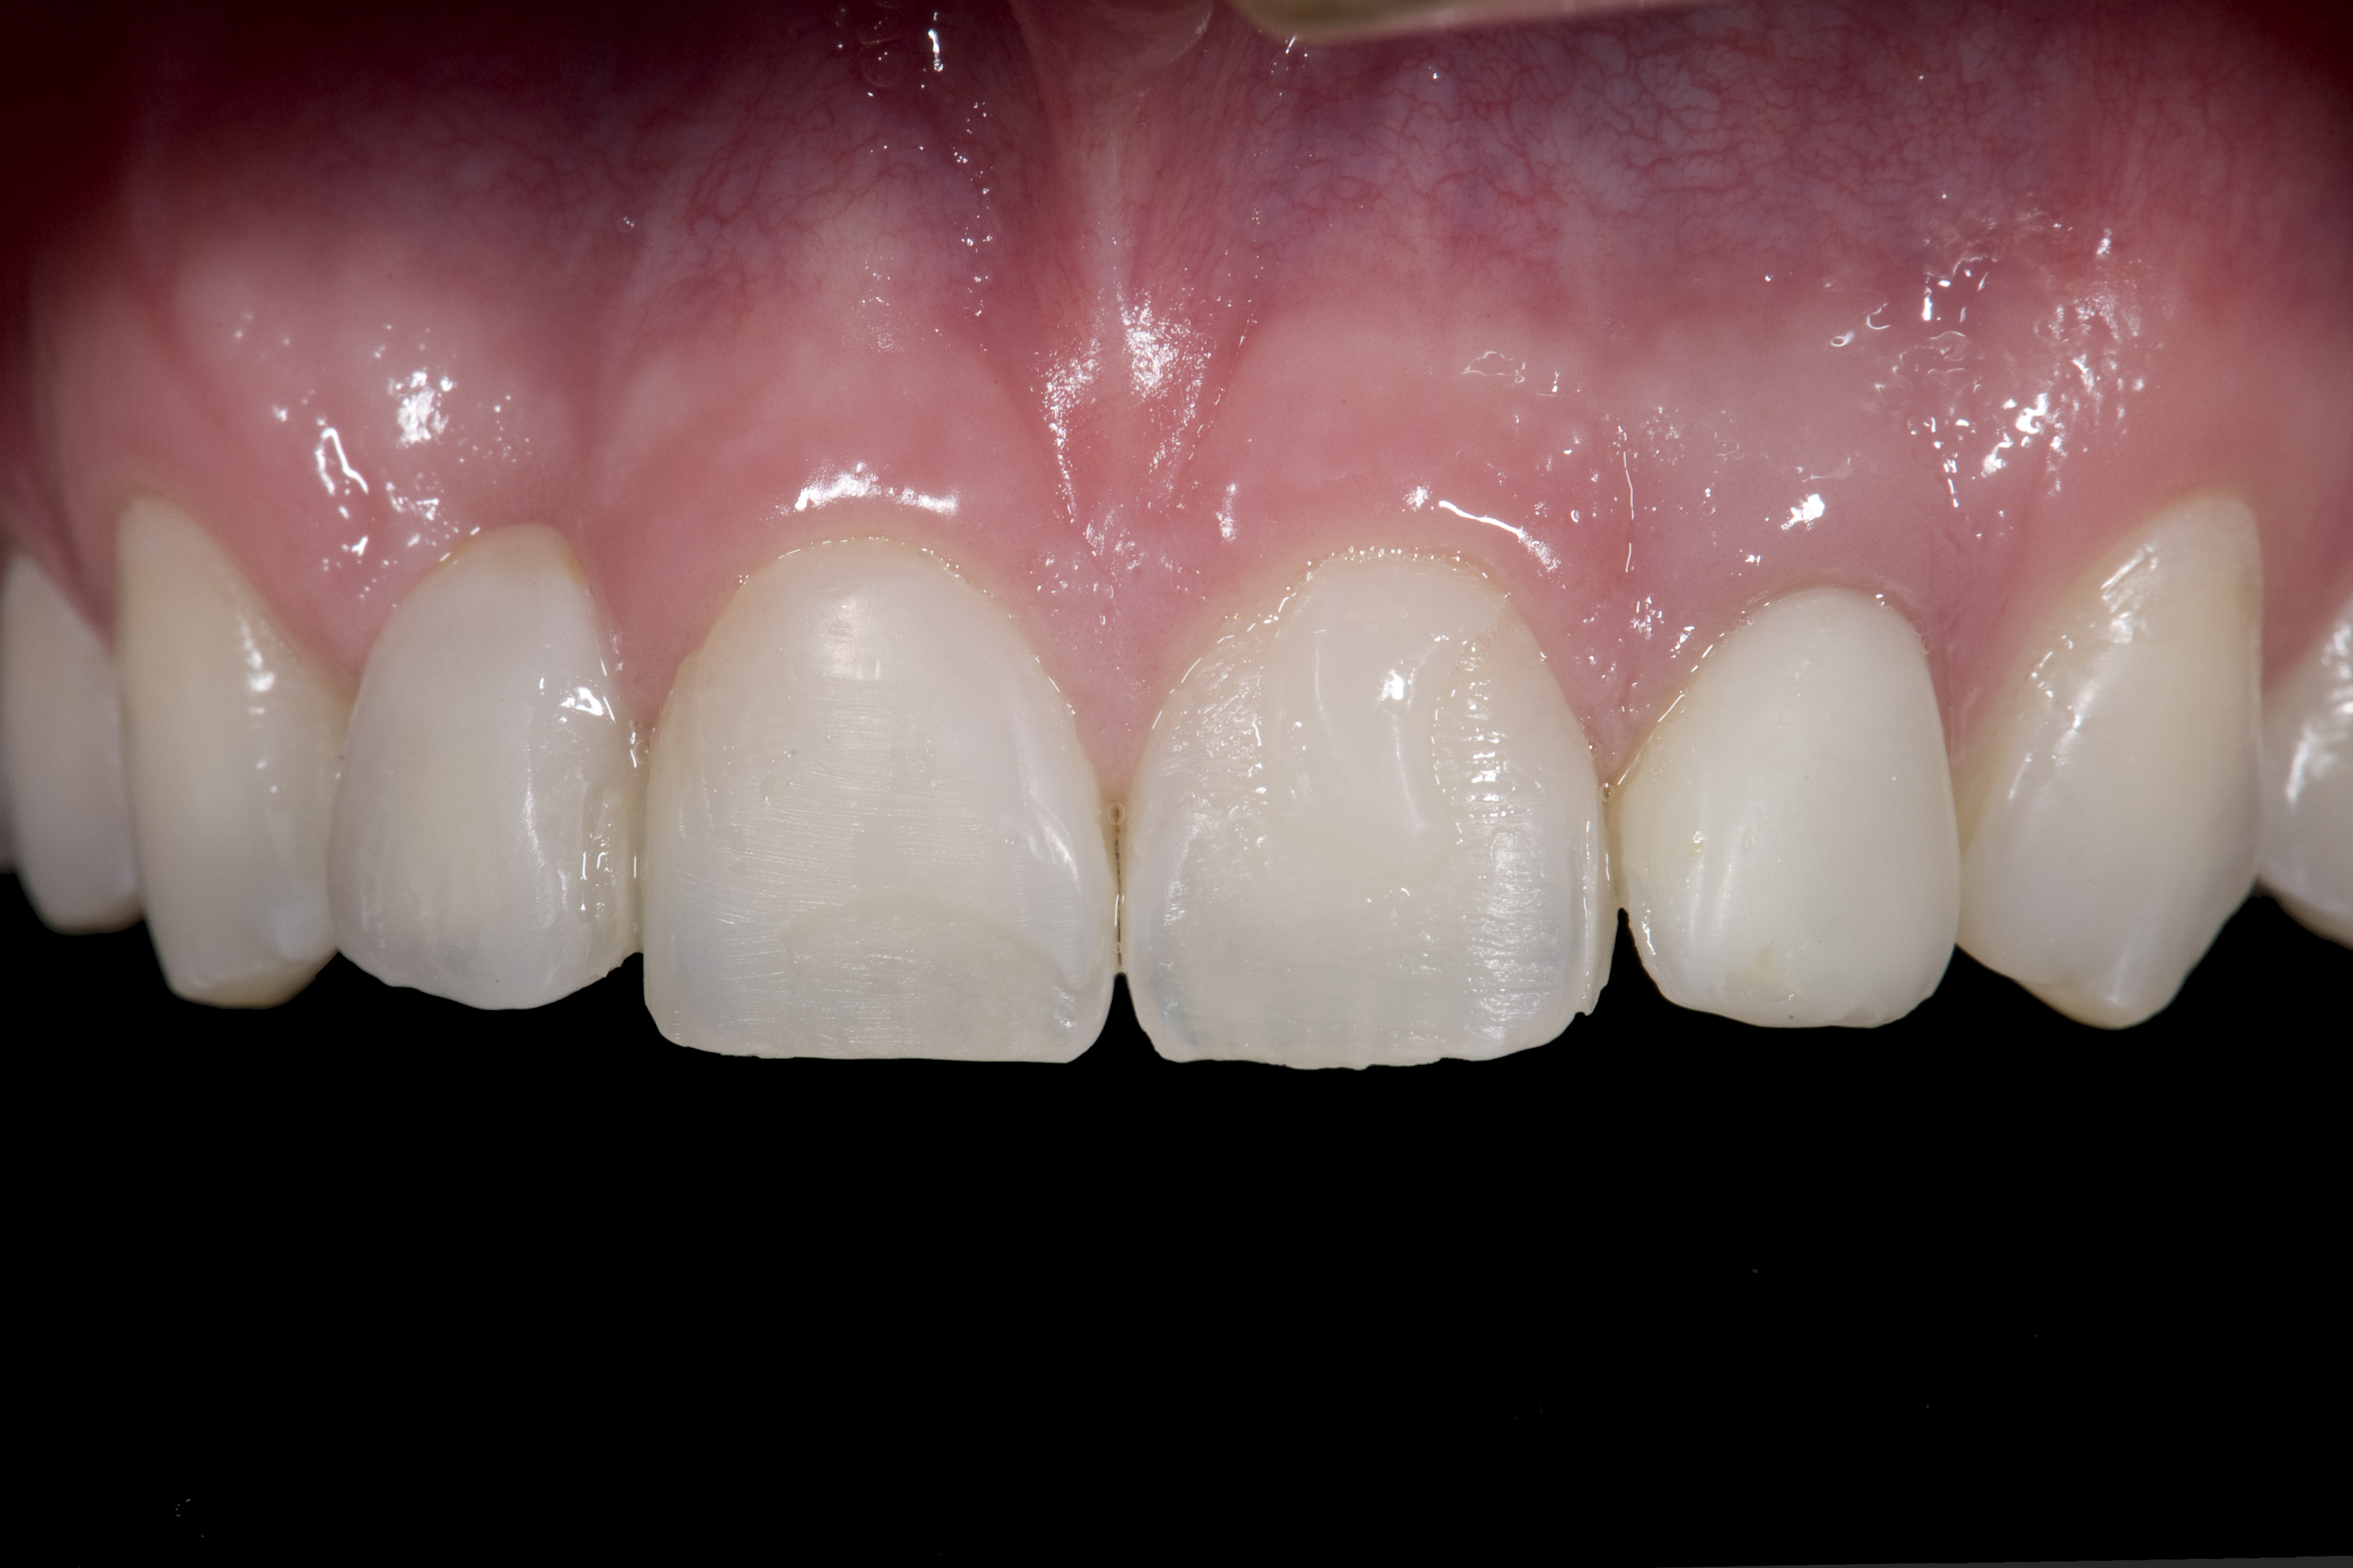

(1.) Initial presentation. Note midline shift to right, missing right lateral incisor, and diminutive left lateral incisor in crossbite.

Figure 1

(2.) After orthodontic alignment of teeth and bleaching. Note alveolar deficiency in right lateral incisor site and diminutive left lateral incisor.

Figure 2

A 14-year-old patient presented to the office with his mother (Figure 1). His chief complaint involved the large spaces between the teeth created by his missing right maxillary lateral incisor and his small left maxillary lateral incisor. He desired to replace the missing tooth with an implant and create a beautiful smile. Upon examination, he was found to have a class I canine and molar relationship, but because he had a tooth size/arch size discrepancy and space distal to the right central incisor, the remaining incisors had drifted to the right. The left maxillary lateral incisor was peg-shaped and in a cross bite position. Studies have shown a clear association between congenitally missing teeth and reduced tooth size.59-62 Because he was only 14-years-old at the time and could not have implants placed until the cessation of growth (somewhere in the vicinity of 22 years old), he was sent to the orthodontist for alignment of the teeth.16,17 After 2 years of orthodontics, the appliances were removed, and his tooth coloration was improved using carbamide peroxide bleaching (Figure 2). Because some form of provisional needed to be placed until he was finished growing, a double-wing metal resin-bonded bridge was chosen. As discussed earlier, this is the ideal transitional prosthesis for patients that have congenitally missing maxillary lateral incisors. The benefits of this type of prosthesis include its ability to be removed and rebonded during the surgical phase of treatment and its ability to retain the roots in their proper position after orthodontic treatment.16 The final plan for the patient was to increase the width of the central and the maxillary left lateral incisor, utilizing porcelain laminate veneers to achieve the appropriate width/length ratio of 80%. A wax-up was created to idealize tooth size, a putty matrix was made from the wax-up to facilitate bonding of the incisors, and a non-precious, double-wing metal resin-bonded bridge was fabricated for lateral incisor replacement. Once the teeth were bonded to ideal size, the “Maryland Bridge” was fabricated from a polyvinyl arch impression with the newly bonded teeth (Figure 3). The metal frame was cast from a non-precious alloy to allow for fabrication of a very thin frame and to create a better surface for bonding. After sandblasting the internal aspect of the frame with CoJet™ silica (3M ESPE), accomplishing salinization, and executing cementation with a dual-cure resin cement, a fairly good adhesion to the frame was anticipated.29 The enamel surface was etched with phosphoric acid for 30 seconds, the primer (Single Bond Plus, 3M ESPE) was applied to both the internal surface of the sandblasted framework and the etched enamel, and the bridge was cemented with RelyX™ ARC (3M Espe) dual-cured resin cement (Figure 4 and Figure 5).